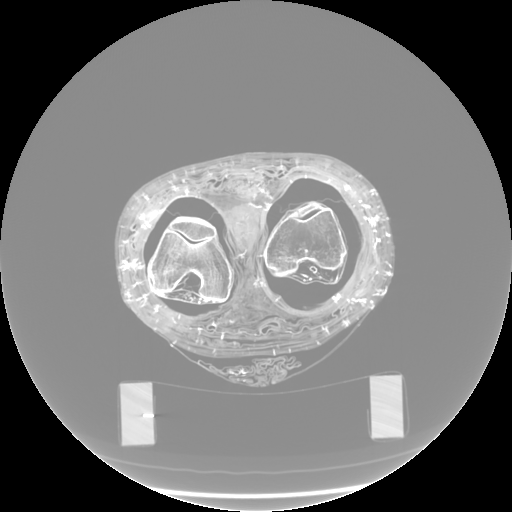

Figure 3: Visualization of axial frames of a mummy [6] selected in proximity of the thigh. (a) Some of the regions we are interested to segment are indicated. (b) Artifacts caused by presence of metals.

In Fig. 3a, we show one axial slice of a male mummy with indication of the regions to be segmented. Fig. 3b illustrates that metals present inside a bandaged mummy generate severe artifacts, which are not present in standard biomedical data.